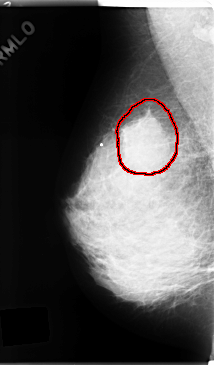

C_0166_1.RIGHT_MLO

RIGHT_MLO LINES 4744 PIXELS_PER_LINE 2776 BITS_PER_PIXEL 12 RESOLUTION 50 OVERLAY

FILE: C_0166_1.RIGHT_MLO.OVERLAY

TOTAL_ABNORMALITIES 1

ABNORMALITY 1

LESION_TYPE MASS SHAPE ROUND MARGINS SPICULATED

ASSESSMENT 5

SUBTLETY 5

PATHOLOGY MALIGNANT

TOTAL_OUTLINES 1

BOUNDARY